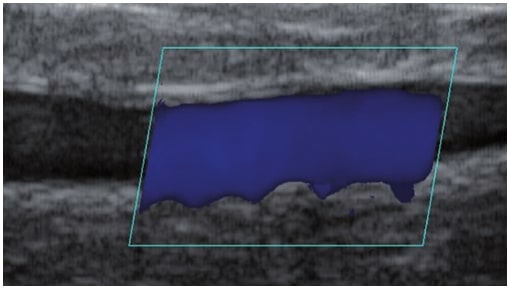

Die Doppler-Sonographie ermöglicht die Darstellung großer Gefäße und Perforatoren, die sich meist in tieferen Bereichen des subkutanen Gewebes befinden. Mit klassischem Ultraschall lassen sich kleinere Gefäße jedoch nicht darstellen. Für die Darstellung kleinerer Gefäße, die oberflächlich unter der Epidermis und im oberen subkutanen Gewebe liegen, wird HFU eingesetzt. Mit Sonden über 20 MHz Frequenz erhält man hochauflösende Ultraschallbilder, auf denen Objekte kleiner als 0,1 mm unterscheidbar sind. Mit zunehmender Auflösung nimmt jedoch die Eindringtiefe ab. Je nach Sonde und Gerät beträgt die maximale Eindringtiefe etwa 20–30 mm. Diese Eindringtiefe bei gleichzeitig hoher Bildauflösung ermöglicht die Beurteilung sehr kleiner Gefäße. HFU erlaubt die genaue Bestimmung des Verlaufs und der Lage kleiner Gefäße in der Haut, was entscheidend für die Wahl der Verschlussmethode und die Planung des Eingriffs ist. Oft sind an der Hautoberfläche nur wenige Gefäße sichtbar – erst durch die Ultraschalluntersuchung lässt sich die tatsächliche Anzahl und der Verlauf feststellen. Für einen erfolgreichen Verschluss muss das gesamte Gefäß behandelt werden, nicht nur der sichtbare Teil, da sonst eine schnelle Rekanalisation erfolgt (7). Häufig ändert das an der Haut sichtbare Gefäß seinen Verlauf, wird gewundener und zieht in tiefere Hautschichten (8). HFU ermöglicht zudem die Darstellung der Perforatoren zwischen kleinen Gefäßen und die Messung grundlegender Parameter wie Durchmesser, Wandstärke, Tiefe und Blutfluss (6). Mit der 40-MHz-Sonde von Ultrasonix kann auch der Blutfluss mittels Farbdoppler visualisiert werden.

Dieses Verfahren überträgt intravaskuläre Techniken aus der Behandlung großer oberflächlicher Venen auf die Mikroebene. Ein Laserfaser wird in das Gefäß eingeführt und koaguliert das Gefäß mit Laserenergie (7,11). HFU ist für die korrekte Durchführung unerlässlich, da es Verlauf, Anatomie, Faserposition, Koagulation und Erfolg des Eingriffs überwacht.